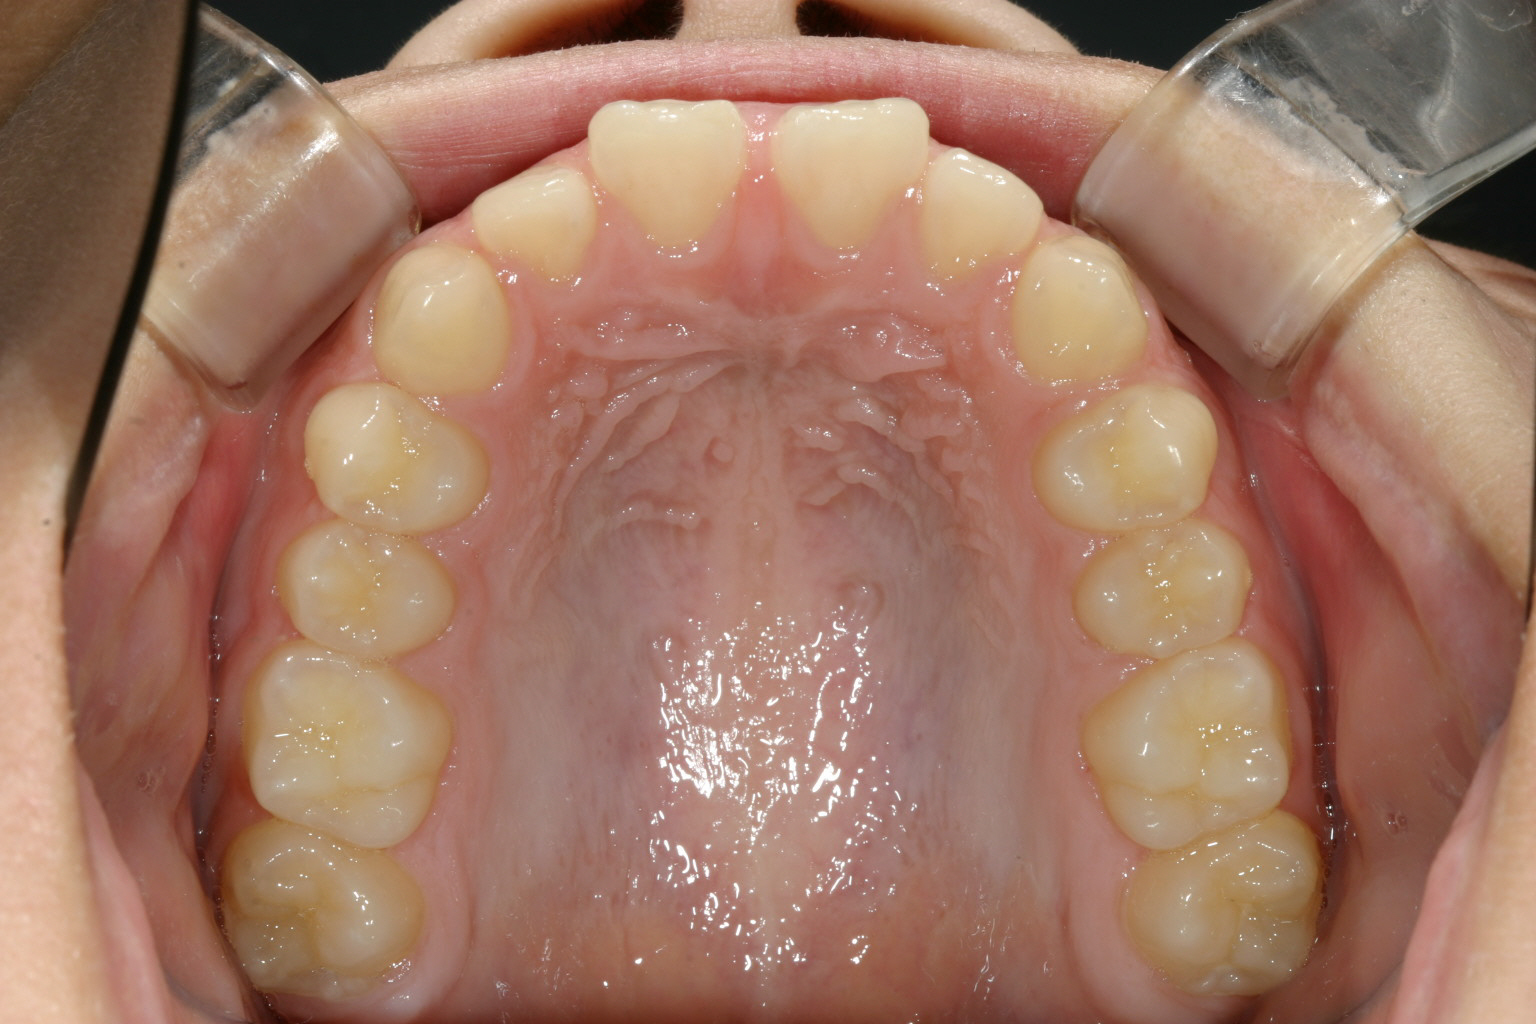

歯列はそう悪くはないですが、真ん中に隙間が目立ちます。

上顎の隙間綺麗に閉じました。